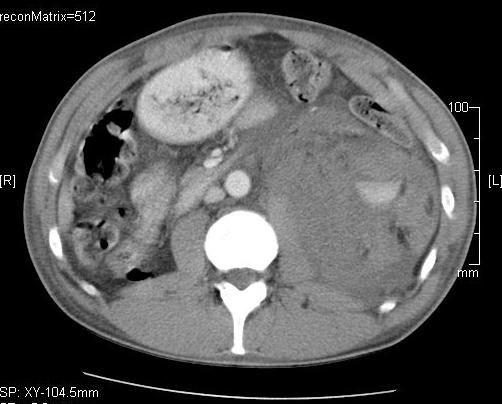

19.2.2.2. CT guided biopsy

Ideal method if the lesion is located either in the chest (figure 5.), mediastinum, retroperitoneum (figure 6.) or the pelvis.

Figure 6. – CT guided pancreatic biopsy